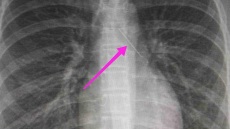

Ανήλικη κατάπιε καρφίτσα στη Θεσσαλονίκη, είχε σταθεί στον αριστερό βρόγχο Η ανήλικη μεταφέρθηκε στο Ιπποκράτειο, υπεβλήθη σε βρογχοσκόπηση και στη συνέχεια οι γιατροί αφσαίρεσαν επιτυχώς την καρφίτσα 31.01.2022, 15:41